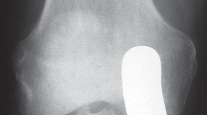

التصوير الطبي ضروري لتأكيد التشخيص وتحديد مدى تلف المفصل:

-

الأشعة السينية العادية (Plain Radiographs):

- المنظر الأمامي الخلفي (AP): يُظهر الركبة من الأمام.

- المنظر الجانبي (Lateral): يُظهر الركبة من الجانب.

- المنظر الخلفي الأمامي المثني (PA Flexed): يسمح بتقييم أفضل للجزء الخلفي من الركبة وقد يكشف عن تغيرات أكبر في الحجرة الخلفية الوحشية.

- منظر شروق الشمس (Sunrise/Patellofemoral): لتقييم المفصل الرضفي الفخذي.

- الأشعة السينية الطويلة للطرف السفلي بالكامل (Full-length standing radiographs): من الورك إلى الكاحل، وهي مفيدة جدًا، خاصة إذا تم استخدام تقنيات الملاحة الحاسوبية. تُظهر هذه الأشعة المحاذاة الكلية للطرف السفلي.